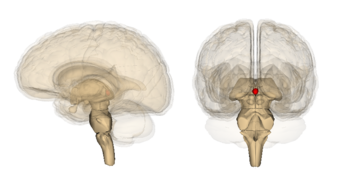

![]() Diagram of pituitary and pineal glands in the human brain  | |

The pineal body is labeled in these images.